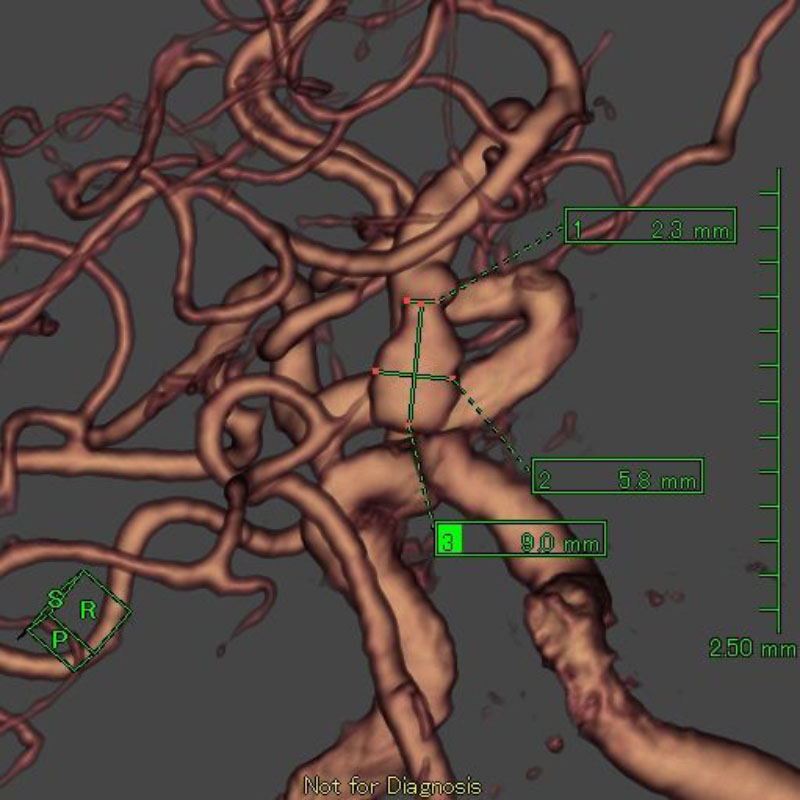

手術前

クリップ前

クリップ後

手術後

右中大脳動脈瘤

クリッピング術

術後血管撮影